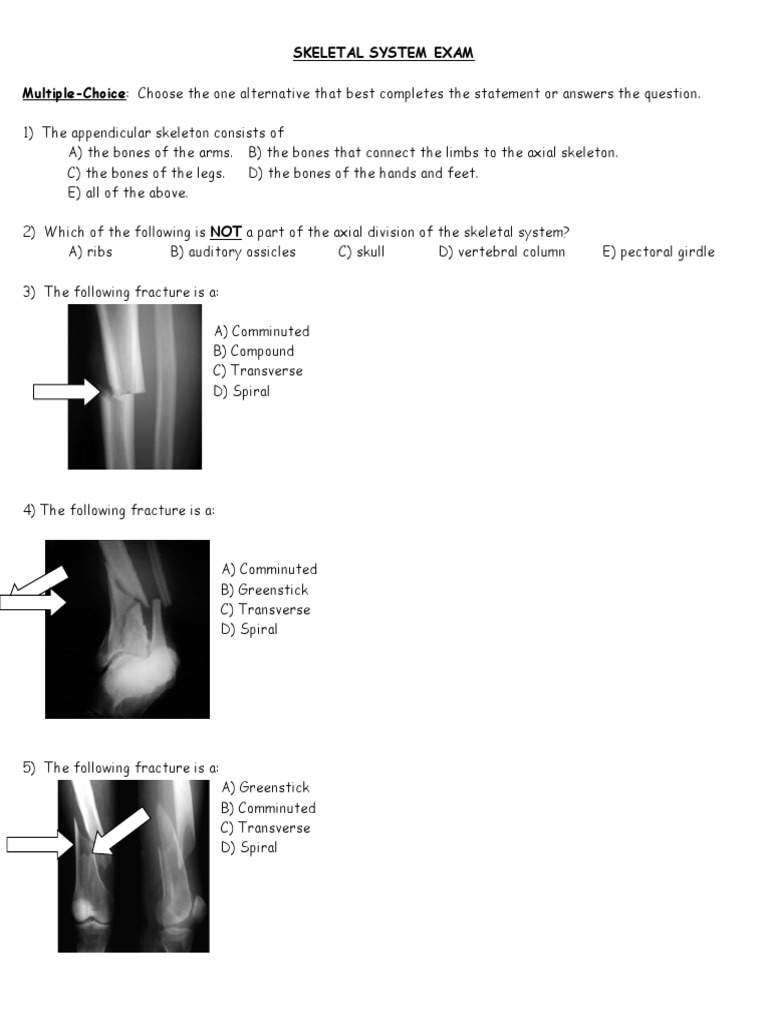

Skeletal System Exam MultipleChoice Choose The One Alternative That Skeletal System Quiz Multiple Choice What parts make up the skeletal system? quiz yourself with questions and answers for skeletal system quiz, so you can be ready for test day. try our top 10 quizzes : Test your knowledge of the bones of the full skeleton. how much do you know about your skeletal system? quiz yourself with questions and answers. Skeletal System Quiz Multiple Choice.